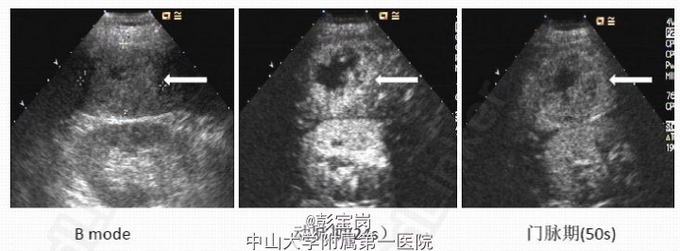

男性,66岁,因“反复右上腹痛1月余”入院。患者于1月余前无明显诱因出现右上腹痛,呈间歇性胀痛,偶伴有右侧腰背痛,可自行缓解,无伴发热、畏寒,无恶心、呕吐等不适,于当地医院就诊,查腹部CT及B超提示“胆囊等回声光团,未除外胆囊Ca并胆固醇沉积,建议行进一步检查”,予消炎、利胆等对症治疗后症状可缓解。为进一步治疗到我院就诊,门诊查腹部B超及超声造影提示“脂肪肝,肝囊肿,胆囊肿大,胆泥形成”。为求进一步手术治疗,门诊拟诊“胆囊炎并胆囊结石”收入我科。